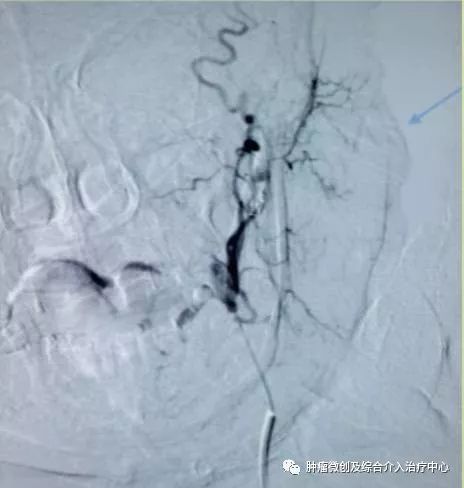

(术前DSA造影提示支气管动脉增粗、增多、絮乱,床表现为咯血,经久不愈)